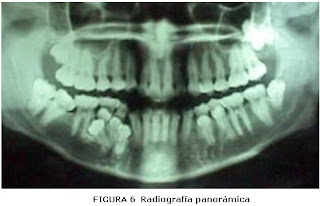

ü Examen

radiográfico.